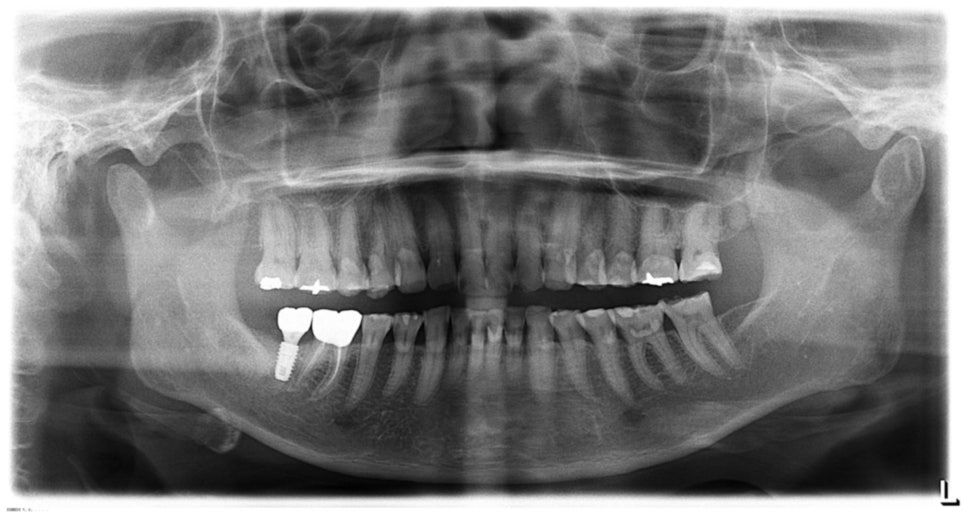

관리 전후 파노라마 사진을 보면 신경치료가 전혀 필요 없음을 확인할 수 있습니다. 일반적인 접근 방식인 '신경을 제거하고 크라운을 씌우는 방법'과는 다른 결과를 만들었습니다.

내원 당시 고객님의 파노라마 사진